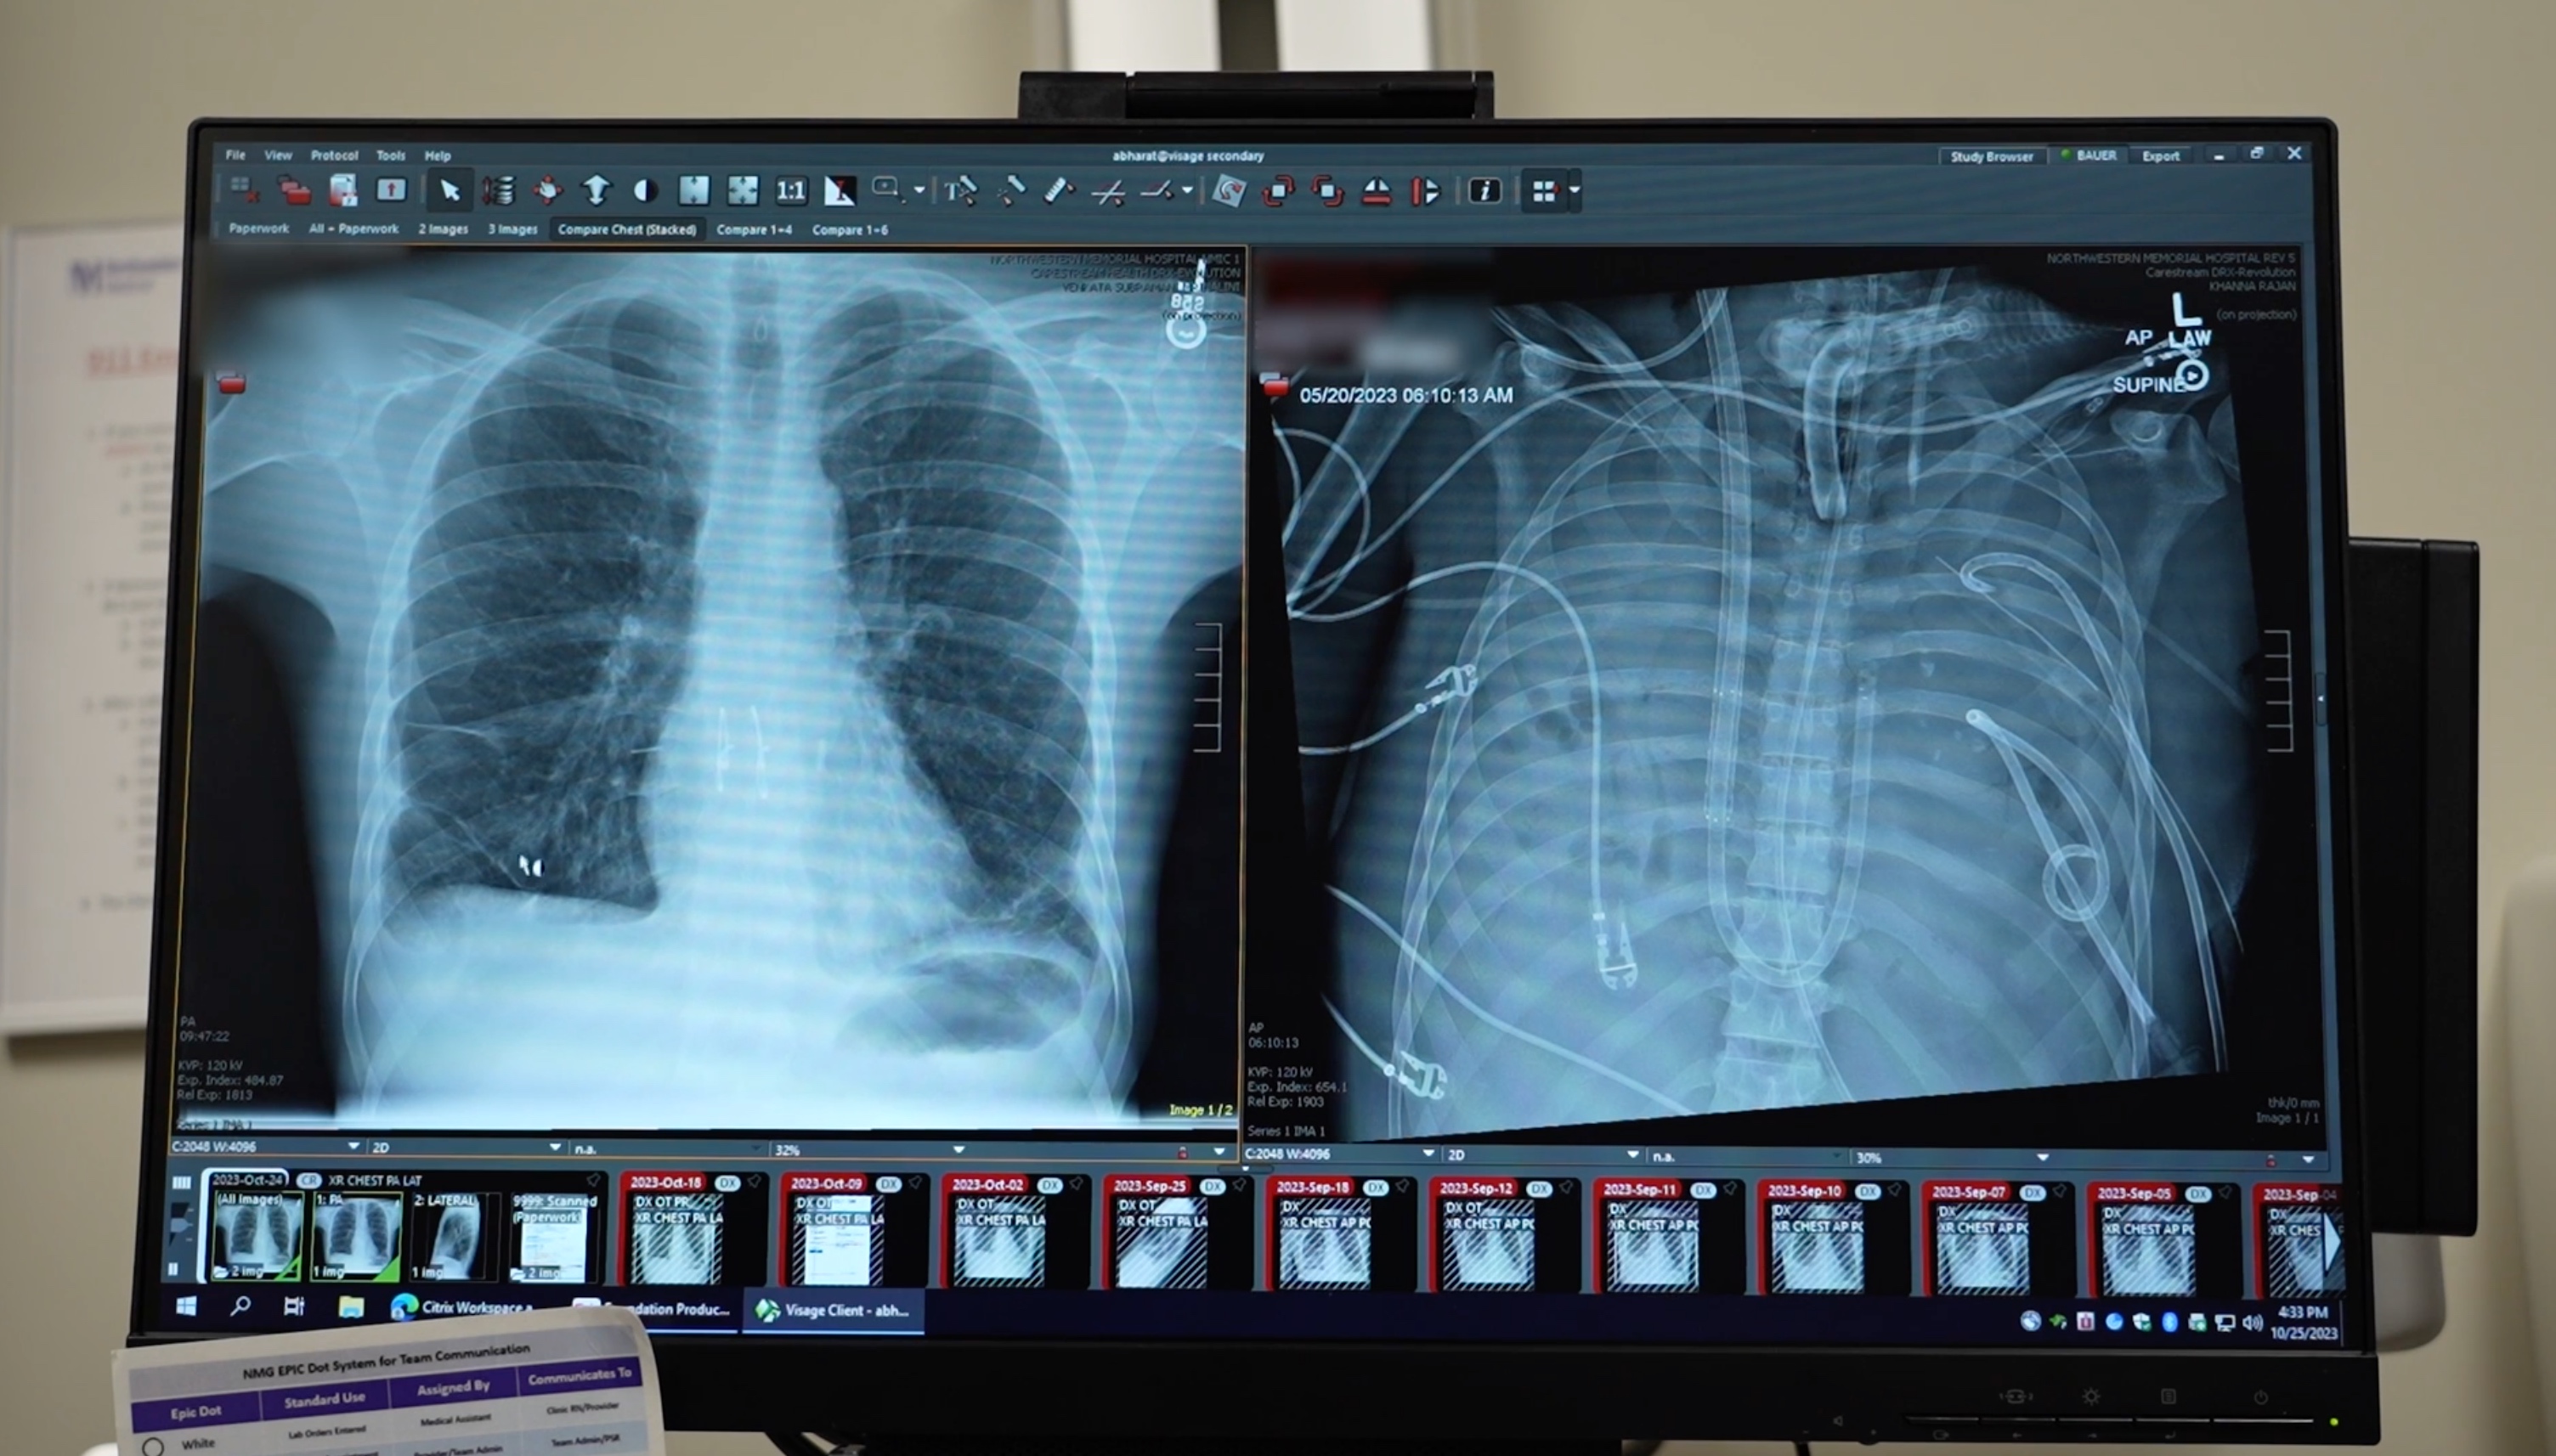

The patients’ new lungs (left) and old lungs (right).  Credit Northwestern Medicine (1), Story by Ben Kaldi - Australian Science Media Centre

US researchers have breathed a sigh of relief after successfully keeping a patient alive for 48 hours without lungs. In their new paper, the team describe an artificial lung system that they used to help a 33-year-old patient 'breathe' for two days after he required both lungs to be removed as a complication of a severe flu infection. The man's lungs deteriorated rapidly due to bacterial pneumonia, so the surgeons decided to on-the-spot engineer an artificial lung system that pumped out the blood, removed carbon dioxide from it, then filled it with oxygen before returning it to the man, bypassing the need for physical lungs, the team say. The man then was able to spend two days recovering from the infection, which the team say was enough for him to be stable enough for a double lung transplant, and now, more than two years later, has returned to daily life with good lung function.

Once the infected lungs were removed, the patient’s condition improved. His blood pressure stabilized, organ function recovered, and the infection subsided. Two days later, donor lungs became available, and the surgeons performed a double lung transplant. More than two years later, the patient has returned to daily life with good lung function.